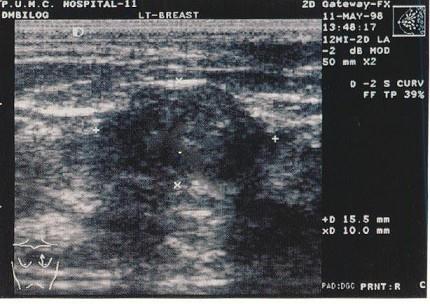

乳腺超声普查发现乳房包块,声像图如上,最可能的诊断是?(?)A.乳腺纤维肉瘤B.乳腺囊性增生C.乳腺癌D.乳腺纤维瘤E.以上都不是

问题 乳腺超声普查发现乳房包块,声像图如上,最可能的诊断是?(?)

选项 A.乳腺纤维肉瘤 B.乳腺囊性增生 C.乳腺癌 D.乳腺纤维瘤 E.以上都不是

答案 D